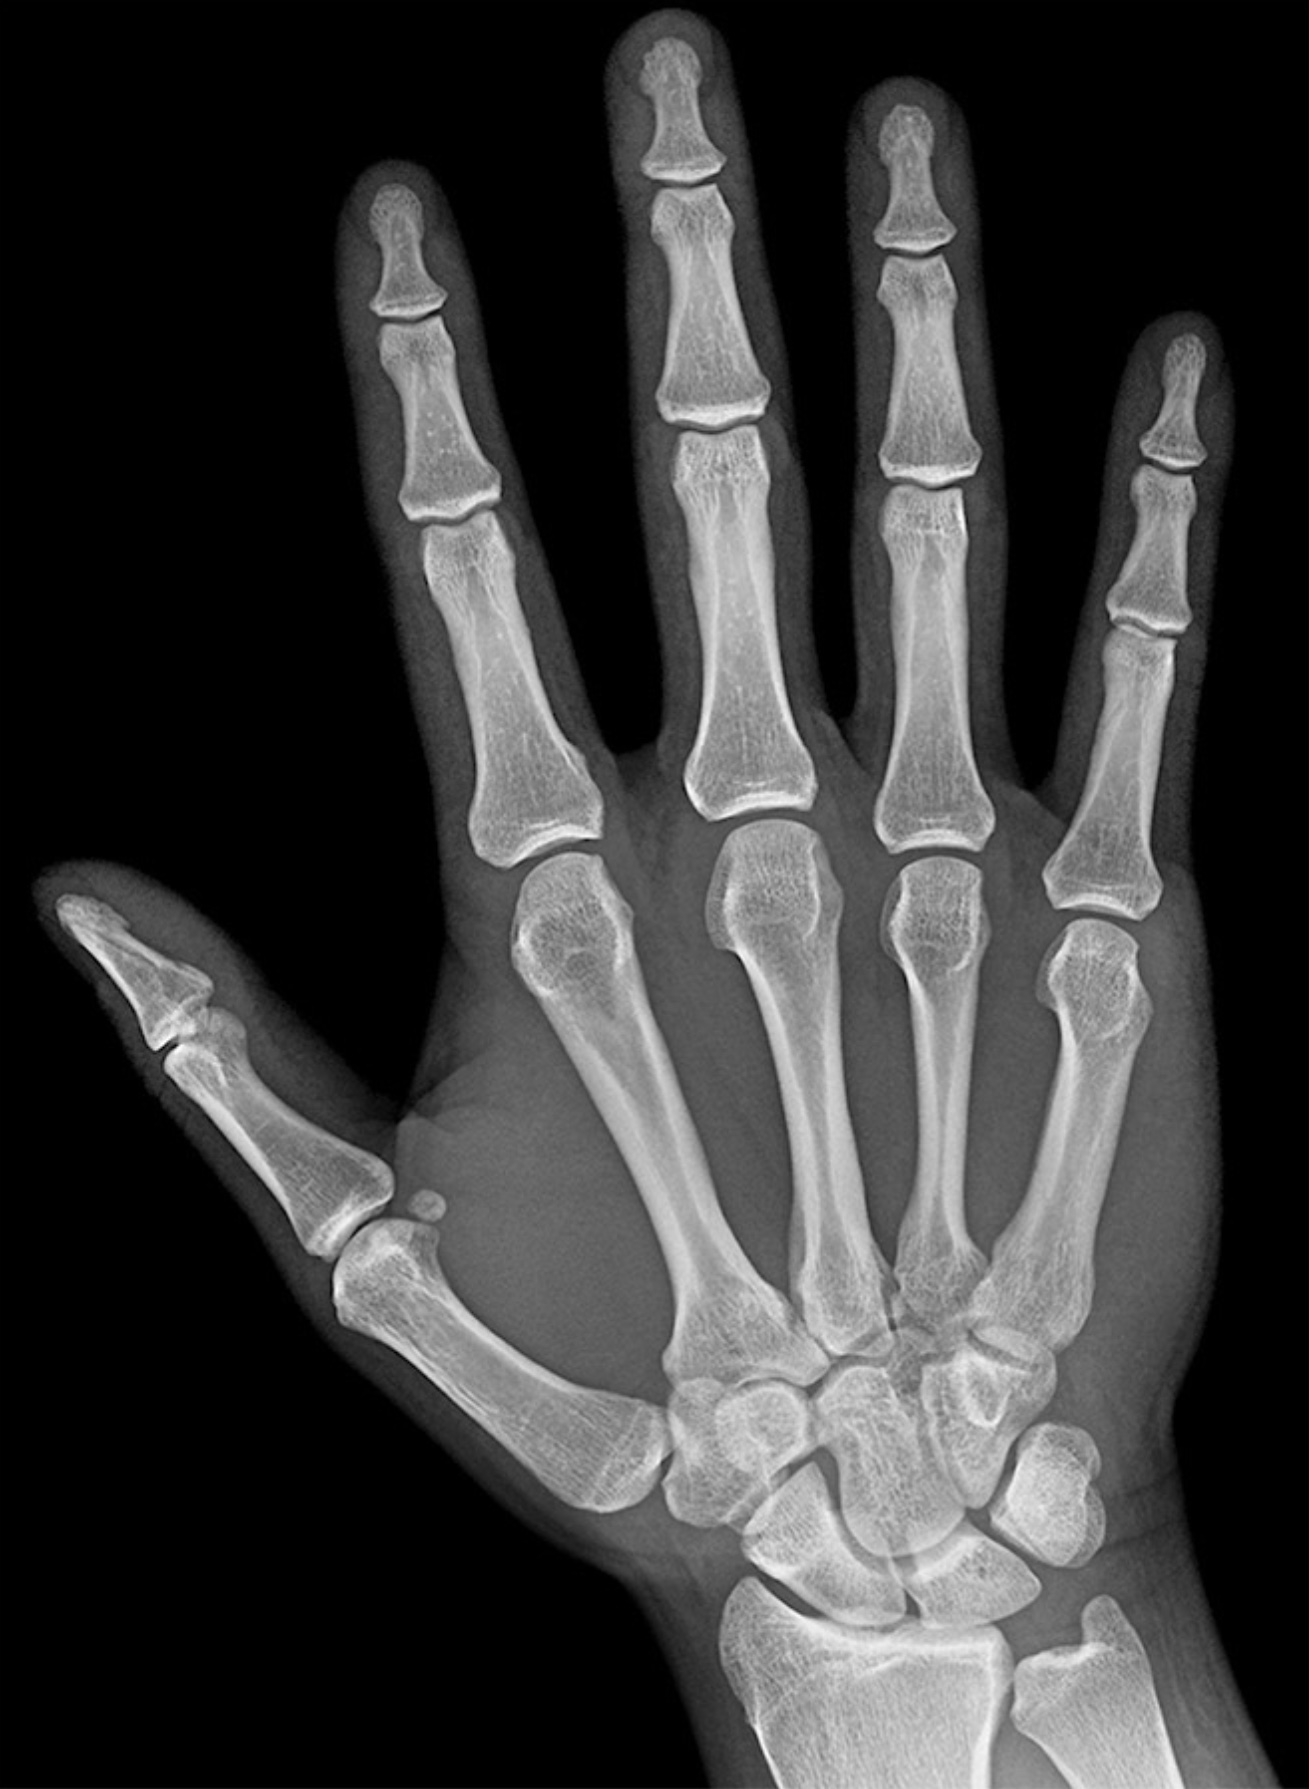

1. A 54-yr-old woman presents with atrophy of the thenar eminence and a lack of sensation on the palmar surface of the radial 3.5 digits. Testing confirms carpal tunnel syndrome with a positive Phalen’s test and Tinel’s test. Describe the boundaries and contents of the carpal tunnel. In your answer, be sure to include the function and innervation of the muscles whose tendons pass through the carpal tunnel. (G. Francis)

1. 34-yr-old male presents to the clinic with diminished sensation and paresthesia of the medial 1.5 digits. The patient just returned from a long distance cycling race. Describe the anatomy of Guyon’s canal. What major motor deficits would the patient present with for compression of Guyon’s canal? Include in your answer the named branches of the nerve involved and why the patient would be able to perceive sensation for the majority of the dorsum of the hand, but have diminished sensation for the nailbeds of the medial 1.5 digits. (G. Francis)

1. A 36 year old receptionist arrives at your clinic complaining of loss of sensation on the lateral side of her hand as well as decreased functionality of her hand. Upon observation you note that her resting hand is displaying the ape hand deformity. After running several tests you confirm that the patient has carpal tunnel syndrome. Explain the anatomy associated with the ape hand deformity. In your answer include the nerve(s) affected, areas of sensory deficits, muscles affected, and the signs that were present indicating the ape hand deformity.